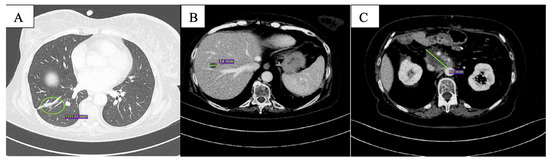

After the first two months of therapy, the patient displayed complete response on the lung metastases (Figure 2A); overall, partial response was documented (Figure 2B,C). One single new liver lesion of uncertain origin was documented. After staff consultation, considering the good clinical conditions, the absence of toxicities from treatment, except for G1 nausea per CTCAE v. 5.0 [13], the diameter of the new lesion (<10 mm), and the excellent response obtained on the other lesions, we decided to continue with the same therapy.

Figure 2.

CT scan after the first 2 months of olaparib showing complete response of the nodular lesion in inferior lobe of the right lung (A), reduction in size of the hepatic lesion in the 8th segment (B) and of peripancreatic tissue (C).